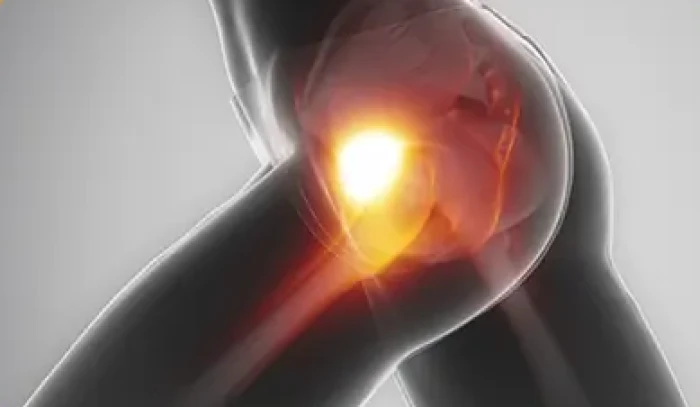

Conflito mecânico na articulação, causa comum de dor no quadril em pacientes jovens.